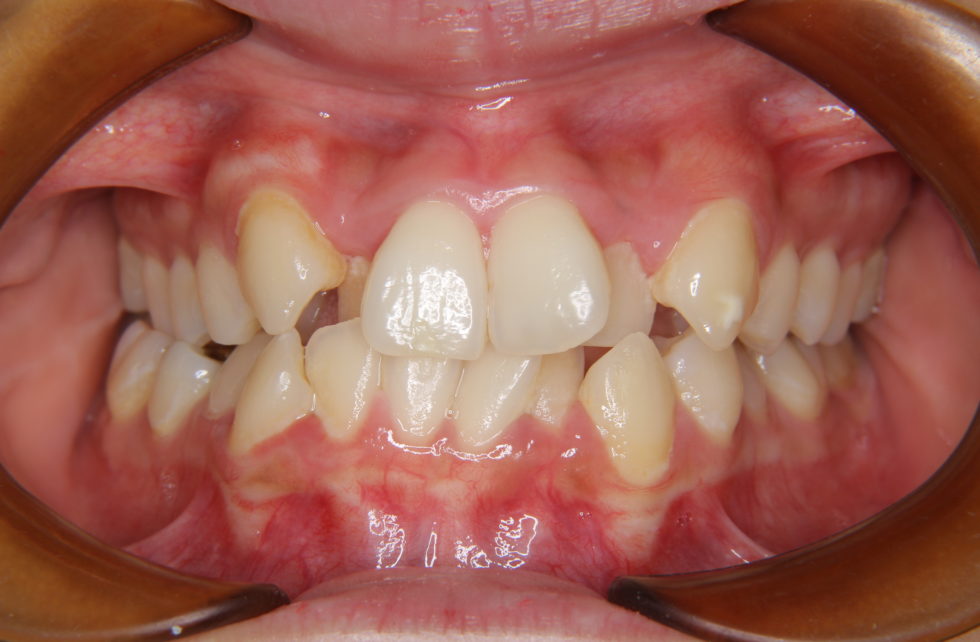

24歳の女性 上下顎前歯の叢生を主訴として来院された。

上顎左右側側切歯が口蓋側、犬歯が唇側に転位し、下顎前歯部も叢生であった。また下顎が右側へ偏位し、右側第一、第二大臼歯が交叉咬合となっていた。上下の正中線もずれが大きく、上顎の正中線が顔面正中より右に約1㎜偏位し、さらに下顎はさらに4㎜程度右側へ偏位していた。下顎の右方偏位と臼歯部交叉咬合を伴う上下顎前歯部叢生と診断した。右側臼歯部の交叉咬合の改善のためクアドヘリックスを先行して6か月間使用し、その後、上下顎小臼歯抜歯を行っていただいて上下顎マルチブラケット装置を使用して動的治療を行った。 動的治療期間2年8カ月間(調整来院24回)